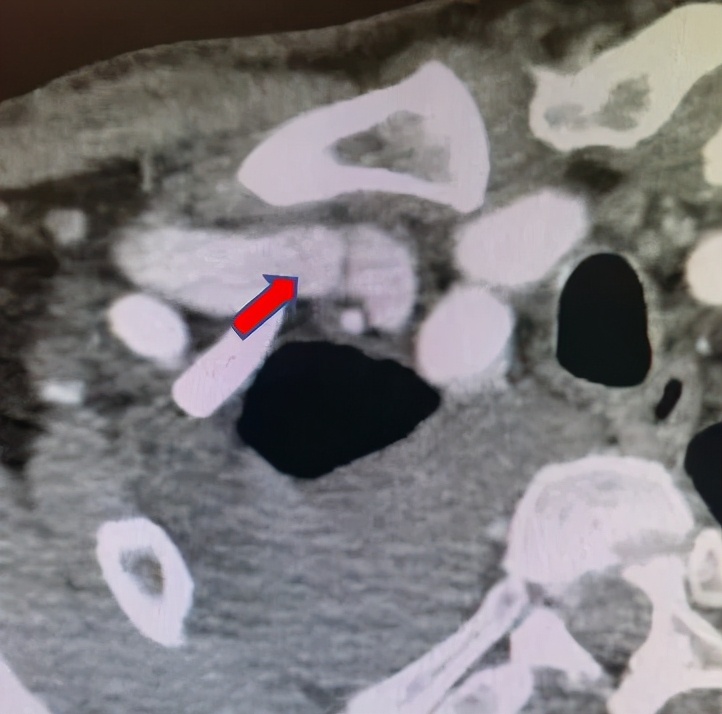

张东亮主任耐心听完患者的叙述,给出了诊断: “肿胀手综合征” 。肿胀手的主要原因是自体动静脉内瘘成型后,静脉发生动脉样改变,管腔内静水压力升高,当静脉血液回流不畅时就会导致压力进一步升高,从而形成患侧手臂显著增粗的病症,这在起搏器植入的血透患者中,发生率更高。张主任立刻为老李安排检查:首先是超声明确内瘘吻合口内径,发现血管流量尚可,静脉弓汇入锁骨下静脉处相对性狭窄伴迂曲。随后又进行了上肢及深静脉CT三维重建(CTA+CTV),发现主要病变为锁骨下静脉汇入头臂静脉处静脉瓣增生狭窄(如下图)